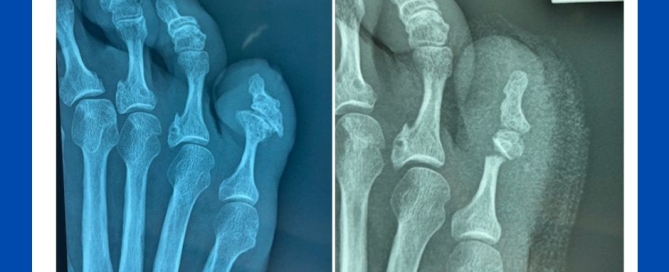

Gout deposits (not bunions)

Blog's main page This patient has presented with concerns about painful bunions. He also suffers from gout. On questioning, he has been less than conscientious with his taking of gout [...]